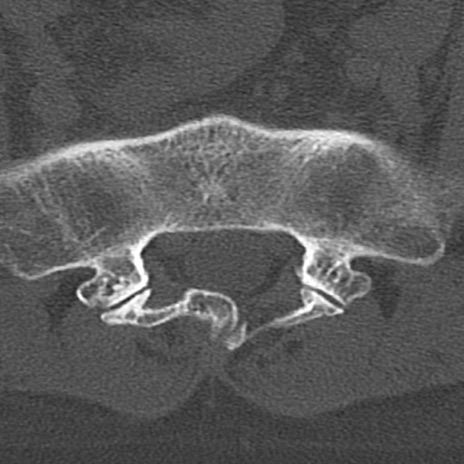

【整形】TIPS症例4 腰椎CT(横断像)

腰椎CT

横断像と矢状断像